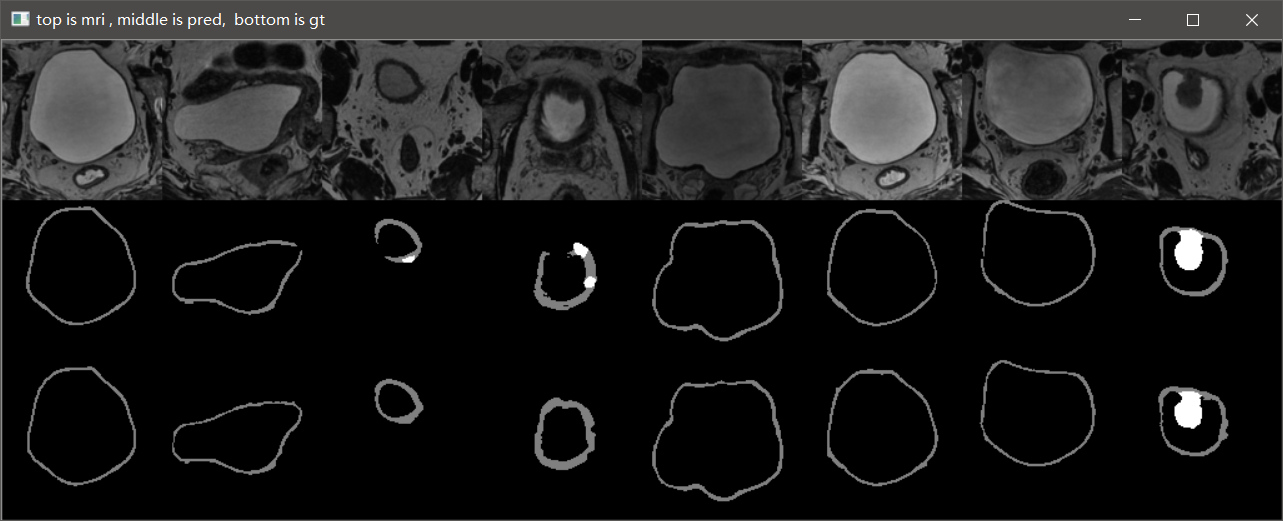

3.10 实验结果

这是笔记本跑了10个epoch的结果,仅仅是测试代码有没有问题。从结果可以看到,代码目前应该是没有问题的,后期只需调参数再训练提升效果即可。

GTX2080TI 跑120个epoch的测试效果:

Val Mean Dice = 0.9051, Val Bladder Dice = 0.9012, Val Tumor Dice = 0.9091